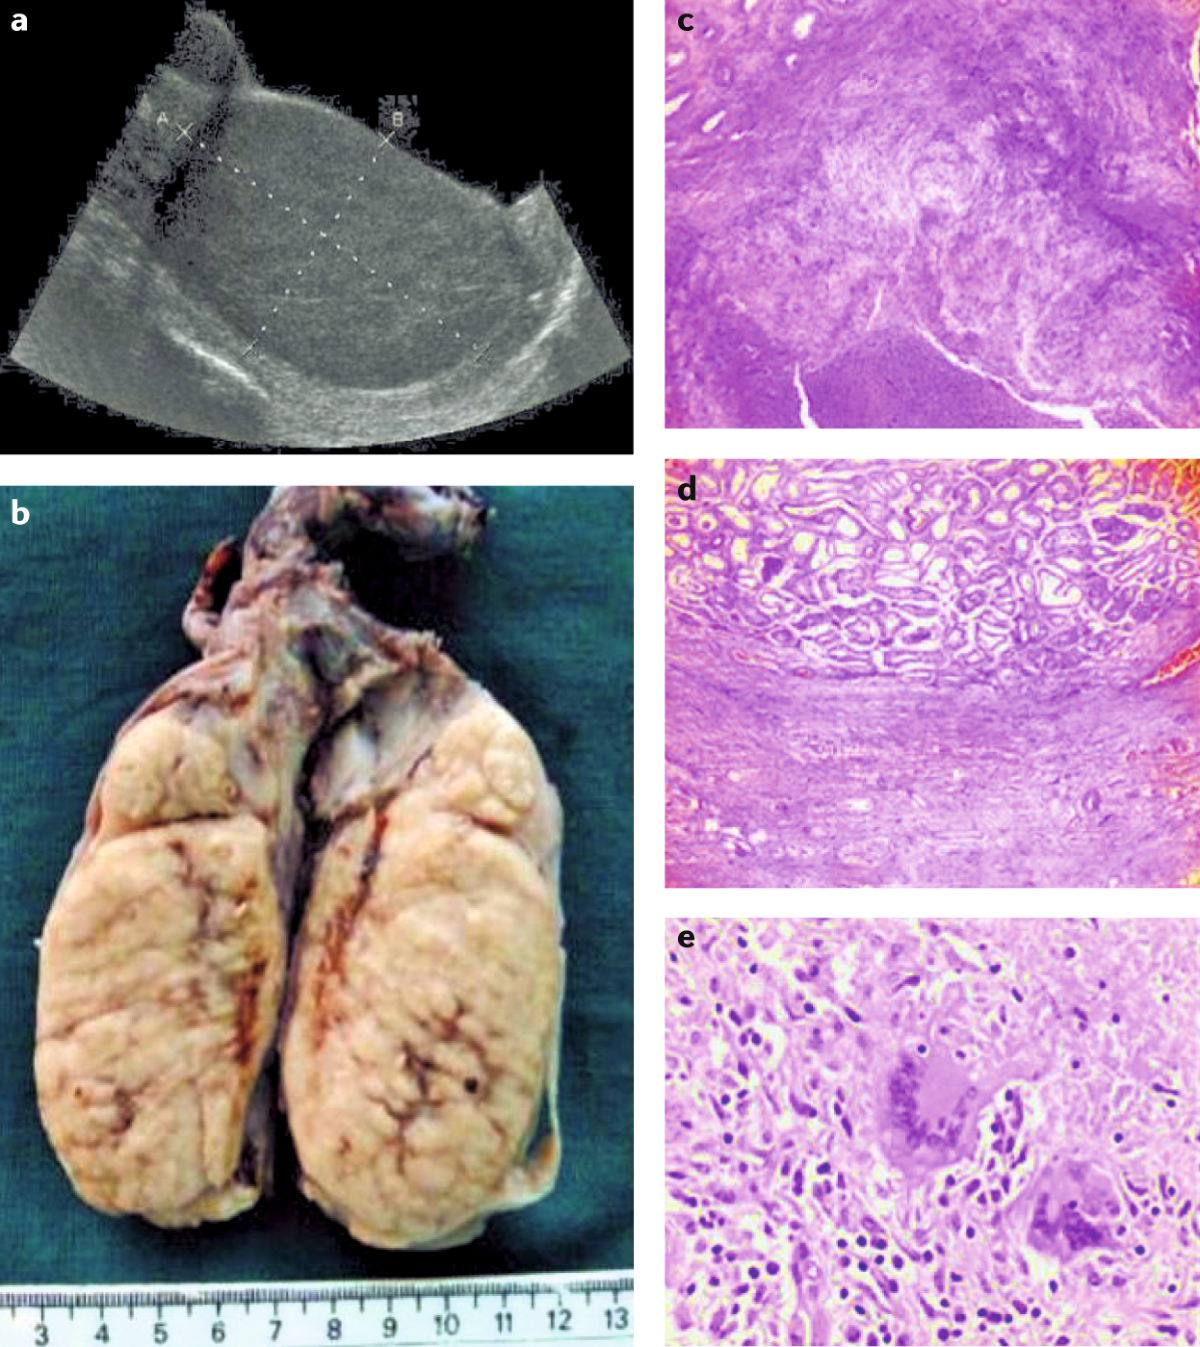

Urogenital tuberculosis — epidemiology, pathogenesis and clinical features | Nature Reviews Urology